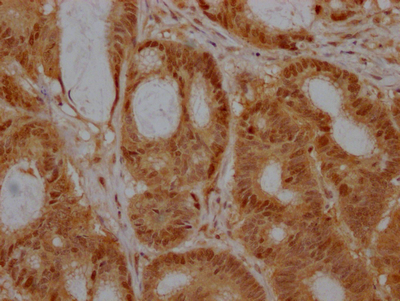

IHC image of CSB-RA218051A0HU diluted at 1:100 and staining in paraffin-embedded human colon cancer performed on a Leica BondTM system. After dewaxing and hydration, antigen retrieval was mediated by high pressure in a citrate buffer (pH 6.0). Section was blocked with 10% normal goat serum 30min at RT. Then primary antibody (1% BSA) was incubated at 4℃ overnight. The primary is detected by a Goat anti-rabbit IgG polymer labeled by HRP and visualized using 0.05% DAB.